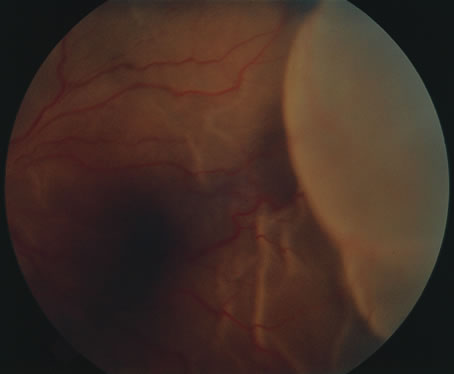

The acute retinal necrosis (ARN) syndrome is most often caused by the herpes zoster virus, although occasionally it may be a result of herpes simplex infection.12 It is typically described in healthy patients although association with immunosuppressed patients has also been described. Granular, nonhemorrhagic areas of retinal necrosis may be observed in the fundus, often rapidly coalescing with resulting blindness often caused by retinal detachment. There is often an associated vasculitis and vitritis. In immunocompromised patients VZV or HSV retinitis may also take the pattern of progressive outer retinal necrosis (PORN) (Fig. 6). PORN differs from ARN in that the former is multifocal, localized to the outer retina, and is less often associated with vasculitis and vitritis.

Fig. 6. Fundus lesions of progressive outer retinal necrosis (PORN). Note the multifocal lesions.